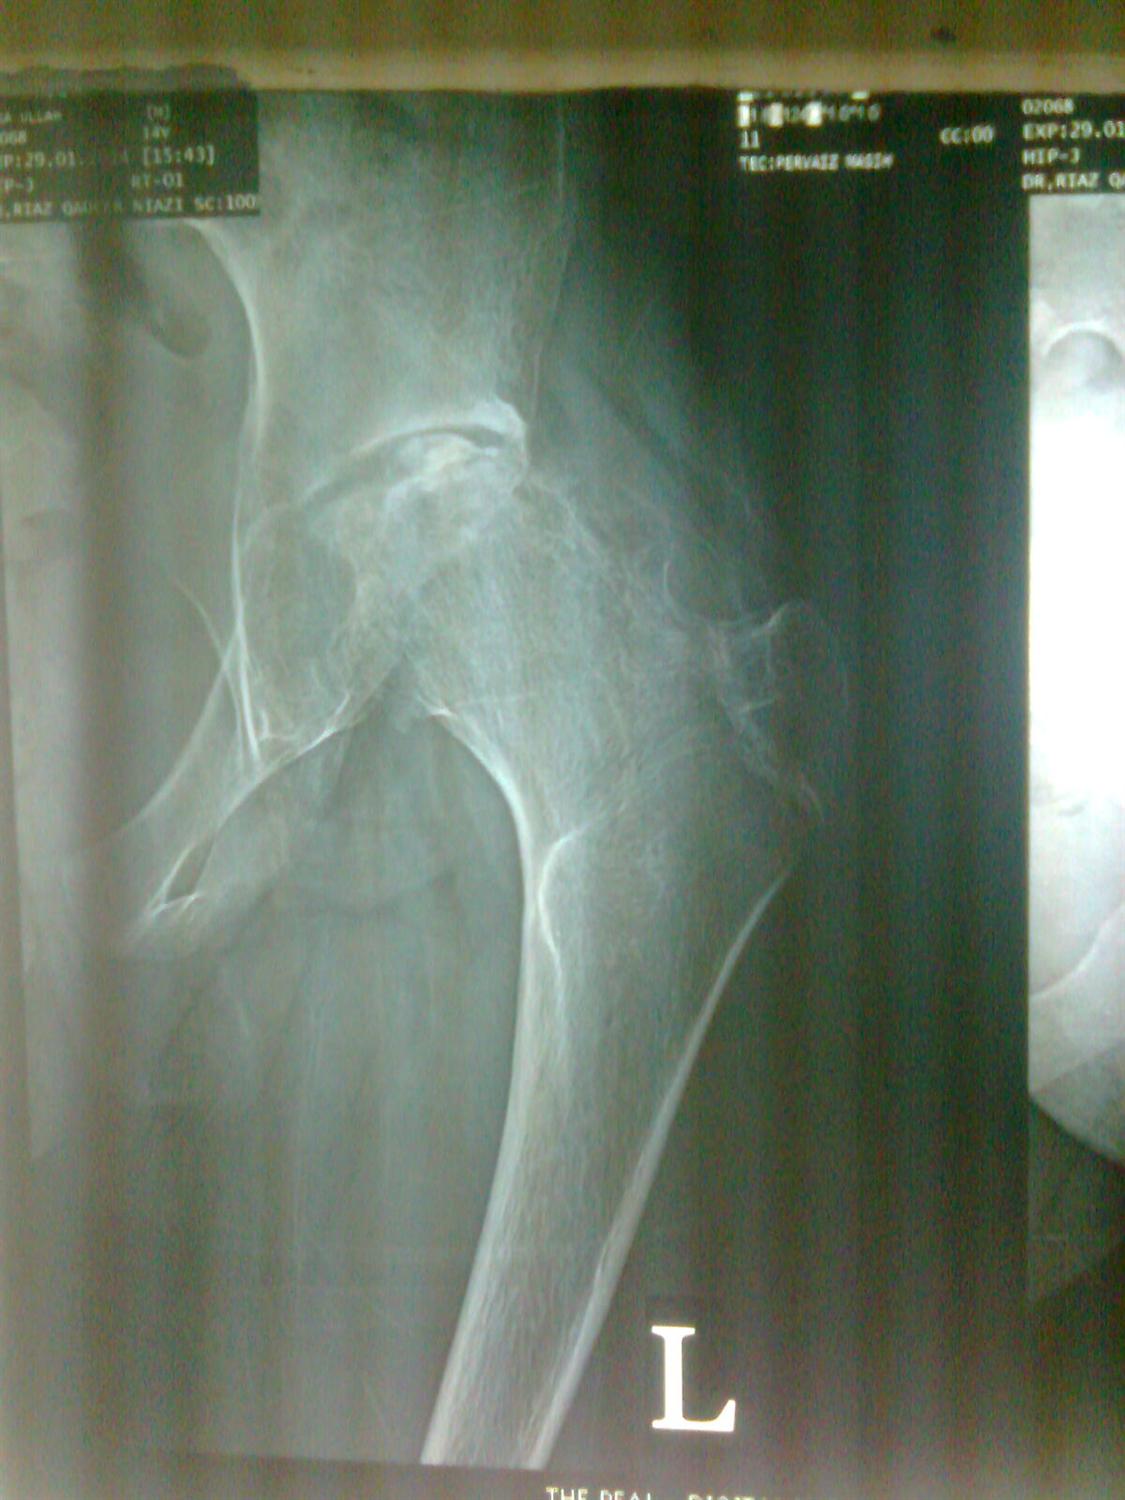

Hip Septic Arthritis Pediatric Pediatrics Septic Arthritis Treatment Orthobullets Medical history is significant for poorly controlled type ii diabetes mellitus. The epidemiology, microbiology, clinical manifestations, diagnosis, differential diagnosis, and treatment of septic arthritis of. On physical exam, the right knee is erythematous,. Though uncommon, septic arthritis is an orthopedic emergency that can cause significant joint damage leading to increased morbidity and mortality. Aureus should be treated with drainage or. Septic Arthritis Treatment Orthobullets.